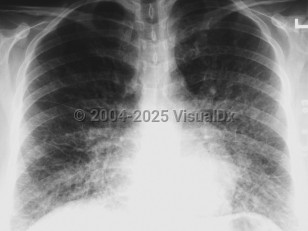

The incubation period for HCPS is 1-6 weeks but usually lasts for 2 weeks. Initial symptoms include the sudden onset of 3-5 days of fever, dry cough, fatigue, dizziness, myalgia, headaches, chills, nausea, vomiting, and abdominal complaints. The gastrointestinal symptoms can at times be severe and mimic surgical emergencies such as appendicitis, cholecystitis, or diverticulitis. Arthralgias and back pain occur less frequently. The disease progresses rapidly to fever, severe coughing, dyspnea, tachypnea, tachycardia, rales, diffuse pulmonary edema, acute respiratory distress syndrome (ARDS), and death. Rarely, some patients may develop disseminated intravascular coagulation (DIC). At the time most patients seek medical care, they usually require immediate intubation and mechanical ventilation.